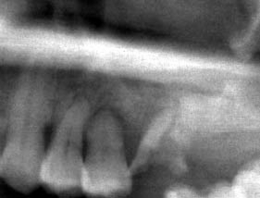

ソケットリフト症例(治療前後のCTもしくはパノラマ写真)

↓

↓